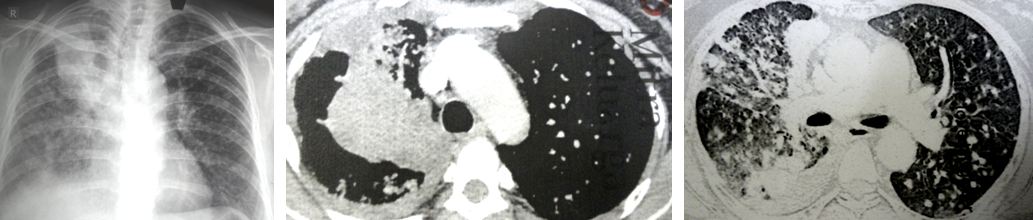

GT went back to the TCM  hospital again. She did a CT scan. The lump in her breast had grown bigger, to 3.8 x 1.8 cm. The cancer had spread to her lungs and bone. Unfortunately, GT did not bring along her CT scan so I am not able to see the extent of her metastasis.

3. Now, the cancer has already spread to your lungs and bone. I don’t know how extensive it is because you did not bring along your CT scan.